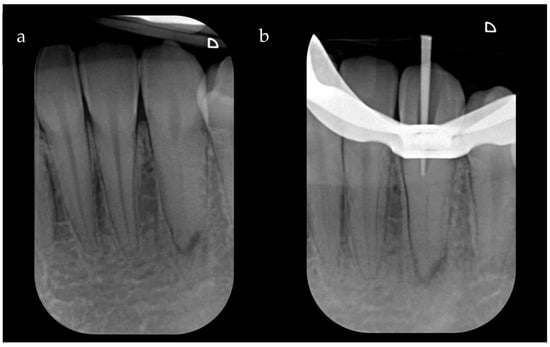

After local anesthesia (Articaine Septanest with adrenaline 1:200,000; Septodont, Saint-Maur-des-Fosses, France), the operating field was isolated with a rubber dam. The correct positioning and stability of the guide were preliminary checked, and the temporary filling material was removed. Once the template was positioned, a 0.8 mm drill (210L16 205 008 Komet Dental Gear Brassier GmbH & Co. KG, Lemgo, Germany) was mounted on the blue ring contra-angle and inserted through the guide cylinder. Once the planned target point was reached, the scouting phase was performed by a K-File #10 instrument (Dentsply Sirona Endodontics, Ballaigues, Switzerland) (Figure 3). The electronic working length was measured using the electronic apex locator (Ai-Pex, Gullin WoodPecker Medical Instrument Co., Ltd., Guilin, China), and a periapical X-ray was performed to confirm the working length. The canal was shaped with rotary Ni-TI files (EdgeEndo Platinum, EdgeEndo, Albuquerque, NM, USA), and the apex was finished with an F3 file (Protaper Ultimate, Dentsply Sirona, Charlotte, NC, USA). Detersion was performed by multiple rinses of 5% sodium hypochlorite (Niclor 5—Ogna, Muggio dental division, MB—Italy). To seal the shaped canal, the single-cone technique with hydraulic cement (Endosequence BC Sealer, Brasseler USA Savannah, GA, USA) was used; the cavity was then provisionally sealed with temporary cement. After four days, the patient did not show any sign of inflammation and symptoms, and restoration was then performed with adhesive (Optioned SoloTM Plus, Kerr Corporation, Orange, CA, USA) and a composite technique (Enamel plus, HFO Micerium, Rosbach, Germany). A final radiograph was performed at the end of the restorative procedures (Figure 4).

Figure 4. (a) Intra-operative X-ray of the K-file inserted at WL after locating the canal. (b) Intra-operative X-ray with the gutta-percha cone test. (c) Post-operative X-ray with completed root canal filling. (d) Radiograph taken after completing the coronal seal. (e) Radiographic control at three months with signs of improvement of the apical radiolucency. (f) Radiographic follow-up at two years with complete healing.